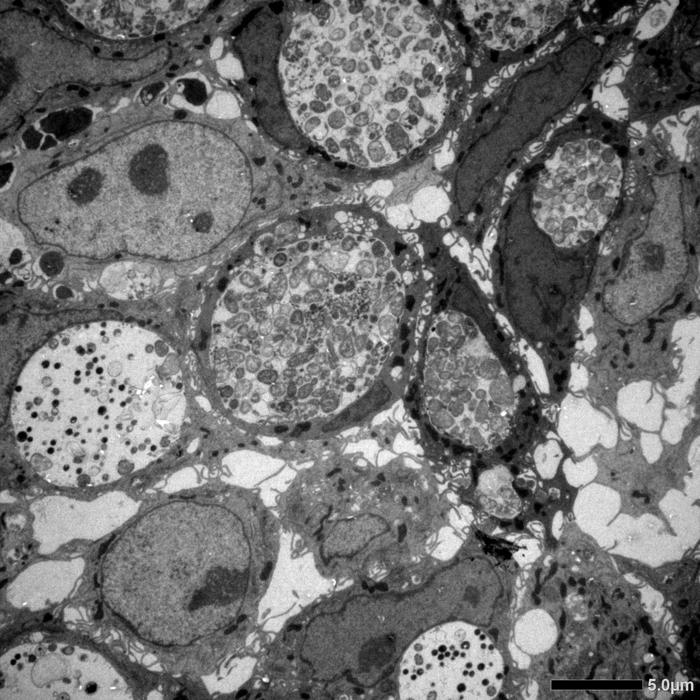

Different Chlamydia Forms in Human Intestinal Cells

Electron microscopy image of human intestinal cells infected with Chlamydia trachomatis and harboring morphologically different forms of chlamydia.

The teams from Würzburg and Berlin tried to infect the intestinal organoids with chlamydia. They discovered that the inner cell layer of the organoids is very resistant to the bacteria: the pathogens could only penetrate there if the cell epithelium was damaged. From the blood side, however, the chlamydia were able to infect very efficiently. "In this case, we repeatedly found the persistent forms of the bacteria, which can be clearly identified with their typical shape under the electron microscope," says JMU researcher Pargev Hovhannisyan, first author of the publication.